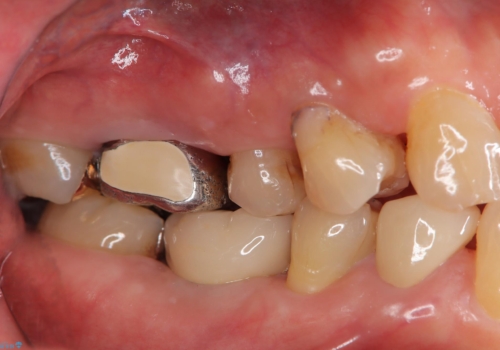

- 定期的に本院に通院されている患者様で、前歯の揺れがあると相談されました。下の奥歯が左右合わせて3本喪失されており、噛み合わせの負担が前歯にも集中していることを説明しました。右下6番の歯に関しては、事前の診査で十分な骨量がありましたのでインプラントを1本埋入しました。左下5番・6番にも本来はインプラントを埋入したかったのですが、骨量が十分でなく、骨を増やす処置をすると神経が近くリスクがあることから、審美性に配慮した金属のばねが見えないノンクラスプデンチャーを製作しました。また、このとき入れ歯を支える左下7番に根尖病変がありましたので、根管治療も行っております。(根管治療は当院院長で専門医を持つDr.林が担当しています。)治療終了後、約1年が経過しましたが、問題なく経過しており患者様も喜ばれていました。